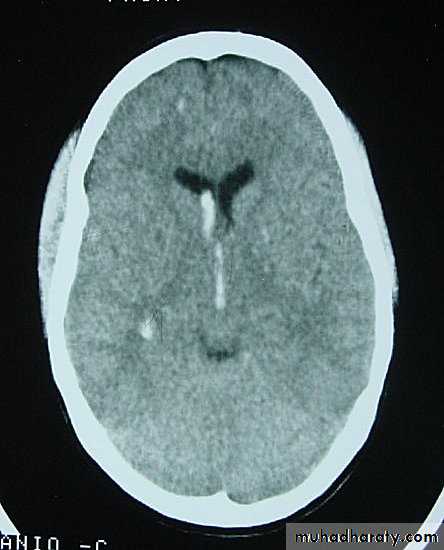

1. Diffuse Axonal Injury

Prolonged post-traumatic state in which there is loss of consciousness from the time of injury that continues beyond 6 hours.Occurs as a result of mechanical shearing at the grey-white matter interface.

This causes disruption and tearing of axons, myelin sheaths and blood capillaries.

Severity can range from mild damage with confusion to coma and even death.